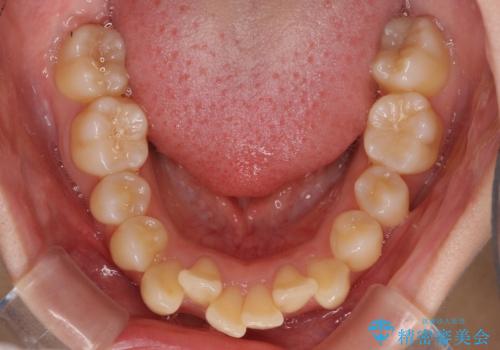

- 上下の出っ歯を気にして来院された患者様です。

口元を積極的に引っ込めるために、上下左右の小臼歯を4本抜歯することとしました。

右上前から2番目の歯が欠損しているため、①矯正治療により欠損部にスペースを作りインプラント補綴を行って前歯を左右対称に揃える、②左右非対称となるが、欠損補綴を行わずに排列する、のいずれかとなりますが、患者様と相談の上②にて矯正治療を行うこととしました。